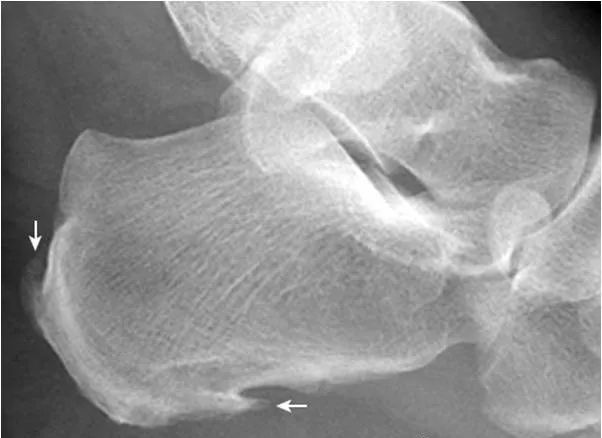

2.Haglund外生骨疣与不典型骨刺:

跟骨后上缘骨刺样突起(箭),属正常变异,称Haglund外生骨疣。穿高跟鞋时可损伤相邻的跟腱,形成Haglund综合征;跟骨结节下缘前突骨刺样突起(箭头),正常人可见,可无临床症状。